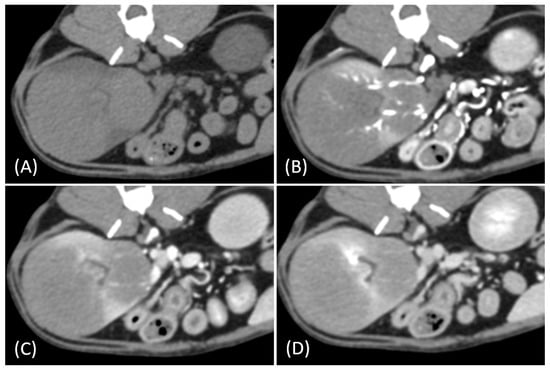

Figure 5.

(A) Pre-contrast, (B) corticomedullary phase, (C) nephrographic phase, and (D) delayed nephrographic/early excretory phase contrast-enhanced computed tomography (CT) images of a cat with primary renal lymphoma. The right kidney shows a unilateral, infiltrative mass with noticeable hypertrophy. The tumor is homogeneous and hypodense, displaying progressive enhancement.

In our study, renal tumor involvement showed distinct patterns in RCC and lymphoma. RCC predominantly presented as solitary and unilateral lesions, with a predilection for the left kidney, whereas lymphoma showed a higher tendency for multiple and bilateral involvement, although unilateral cases were also observed. These findings align with recent studies on feline renal tumors [21,22], suggesting that unilateral involvement in renal lymphoma may be more common than previously recognized.

In our study, one feline presented with primary renal lymphoma, which is extremely rare in cats, with a reported incidence of ˂ 1% of all feline renal neoplasms and 3.6% of all feline lymphoma cases [23,24]. Interestingly, this case showed unilateral involvement differing from the typical bilateral presentation of feline renal lymphoma [14,25]. While primary renal lymphoma is well documented in humans, there is limited literature on its occurrence in cats, with most cases presenting with renal involvement secondary to systemic lymphoma [24,26]. This case highlights the importance of considering primary renal lymphoma in the differential diagnosis of unilateral renal masses, even in the absence of systemic involvement.